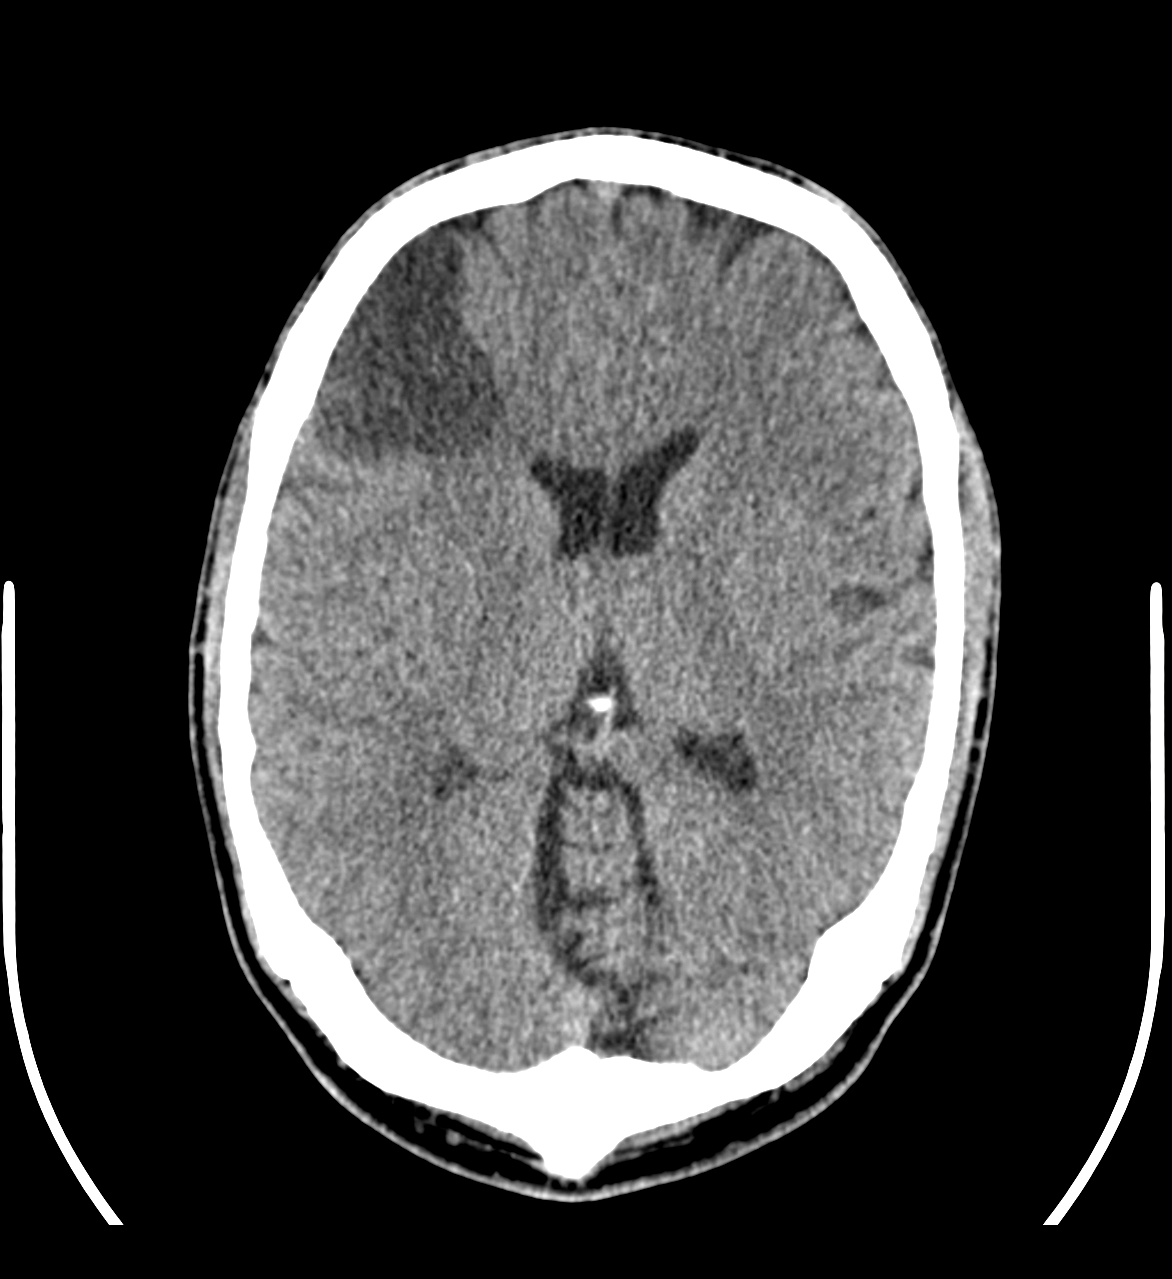

La TC es la prueba de elección de primera línea para lesiones de cabeza en el ámbito de urgencias. Brinda mayores detalles que las radiografías convencionales, sobre todo en tejidos blandos y vasos sanguíneos. Es una técnica fácilmente disponible que se realiza en un periodo de tiempo breve y con un coste razonablemente menor que la resonancia magnética.